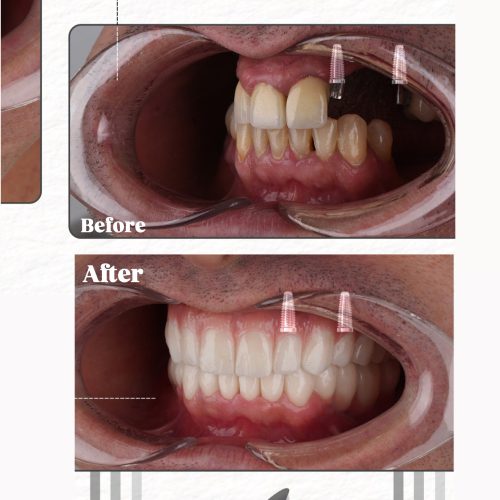

– اوردنچر

– دندان مصنوعی

– ایمپلنت